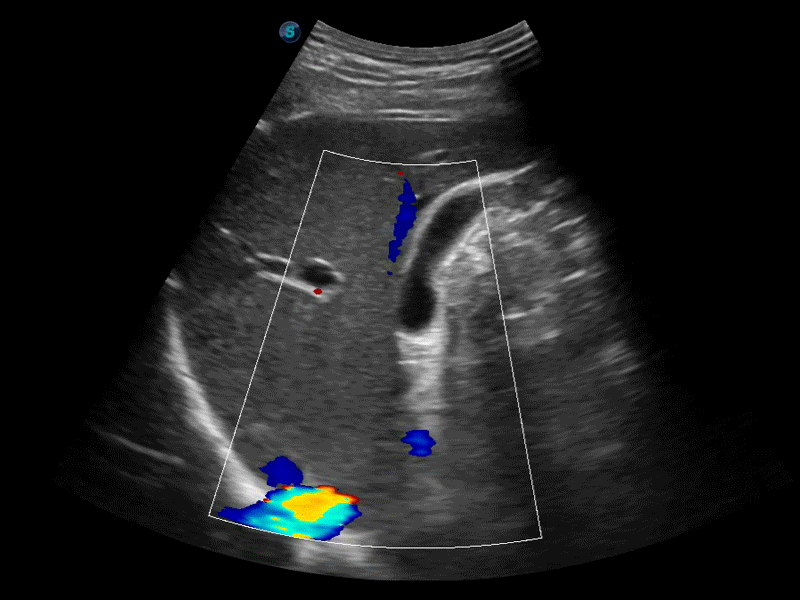

彩色多普勒超声诊断系统

高分辨率血流成像技术提高了对低速血流信号的检测能力。在提高空间分辨率的同时,也克服了血流外溢现象,为用户提供更加真实的血流动力学信息。